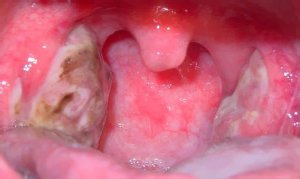

- миндалины увеличены в размерах;

- лимфоидная ткань рыхлая;

- поверхность гланд покрыта большим количеством впадин, которые образовались при удалении гнойных пробок;

- небные дужки отечны;

- иногда выявляется небольшое покраснение слизистой оболочки;

- наличие пробок в миндалинах, которые состоят из омертвевших тканей и бактерий.

- воспаление слизистой оболочки ротоглотки, язычка;

- в лакунах ткани миндалин образуются так называемые гнойные пробки;

- фолликулярный, при котором лимфоидная ткань покрыта мелкоточечными образованиями;

- лакунарный, сопровождающийся образованием обширных пленок на поверхности миндалин;